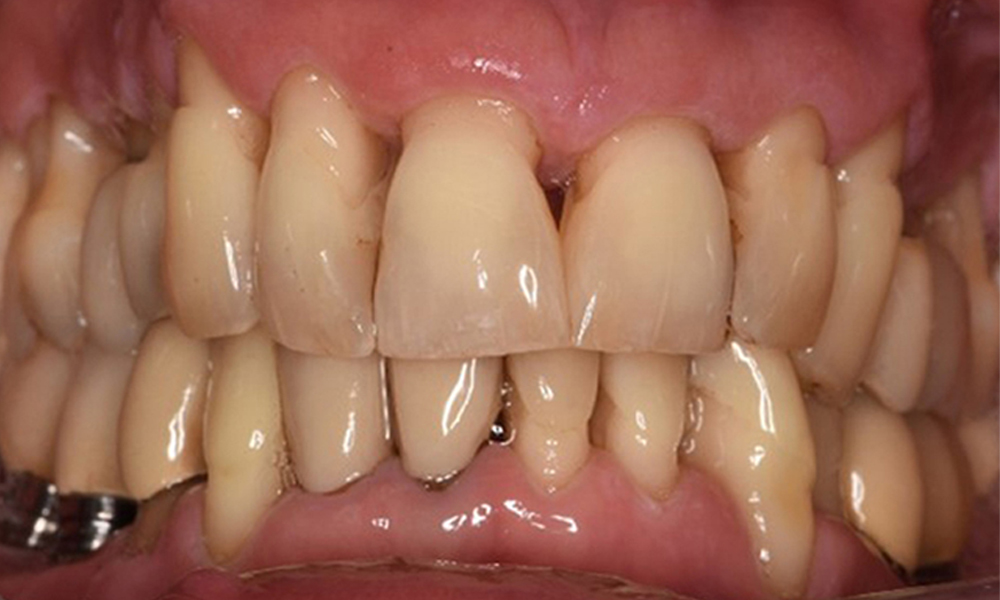

Oral hygiene and patient compliance are very good (see picture “front view”). All that is required is repeat instruction and motivation to maintain oral hygiene behaviour.